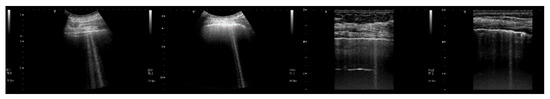

The PVC box, which is shown in the right image of Figure 1, was designed to test the ultrasound response to different distributions of air cylinders. The first test shows what happens when a single row of air cylinders is introduced in the agar gel. The image on the left of Figure 6 shows that in this case, there are no artifacts except the short ones which are generated by multiple reflections between two contiguous air cylinders. In fact, a distance of about 0.5 mm between two replicas of the repetitive pattern can be derived from Figure 6 according to the assumed propagation speed of 1500 m/s. In particular, no artifact is generated by a single air cylinder. The situation changes, however, as a row of air cylinders is added, and increasingly longer artifacts are observed as the number of rows of cylinders increases. The two images in the centre and on the right of Figure 6 show the artifacts which were obtained with two and with four rows of air cylinders, respectively. A repetitive pattern is still perceivable, but it is not clearly quantifiable. The thick white lines at the bottom of the three images are given by the reverberations within the bottom wall of the box.

Figure 6. The image on the left shows how a single row of air cylinders does not generate vertical artifacts. The two images in the centre and on the right show the artifacts obtained with two and with four rows of air cylinders. A different zoom degree has been used for the image on the right.